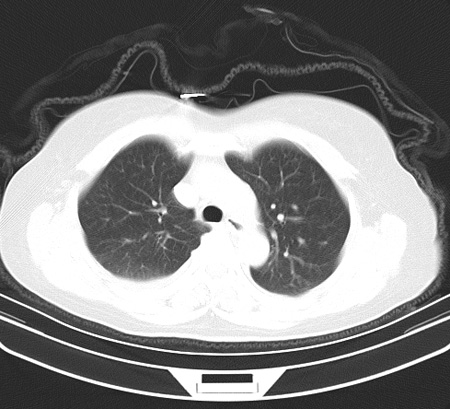

以下是引用余辉在2009-2-19 20:10:00的发言:[br]多考虑急性感染性病变,右中叶尚可见多枚小斑片状影,多为化脓性肺炎,双侧胸腔积液

以下是引用随光逐影在2009-2-19 20:33:00的发言:[br]1)考虑右肺炎症;建议抗炎治疗后复查。2)双侧胸腔积液(以右侧为甚)。

以下是引用花凤凰在2009-2-19 20:46:00的发言:[br]病人有发热,胸痛急性起病,主要病变位于右肺中叶外侧段,呈楔行改变,位于外带胸膜下,考虑为肺梗塞可能!!!!!!!!!!!!!!!!!!!!!!!!!!!!!!!!!!!